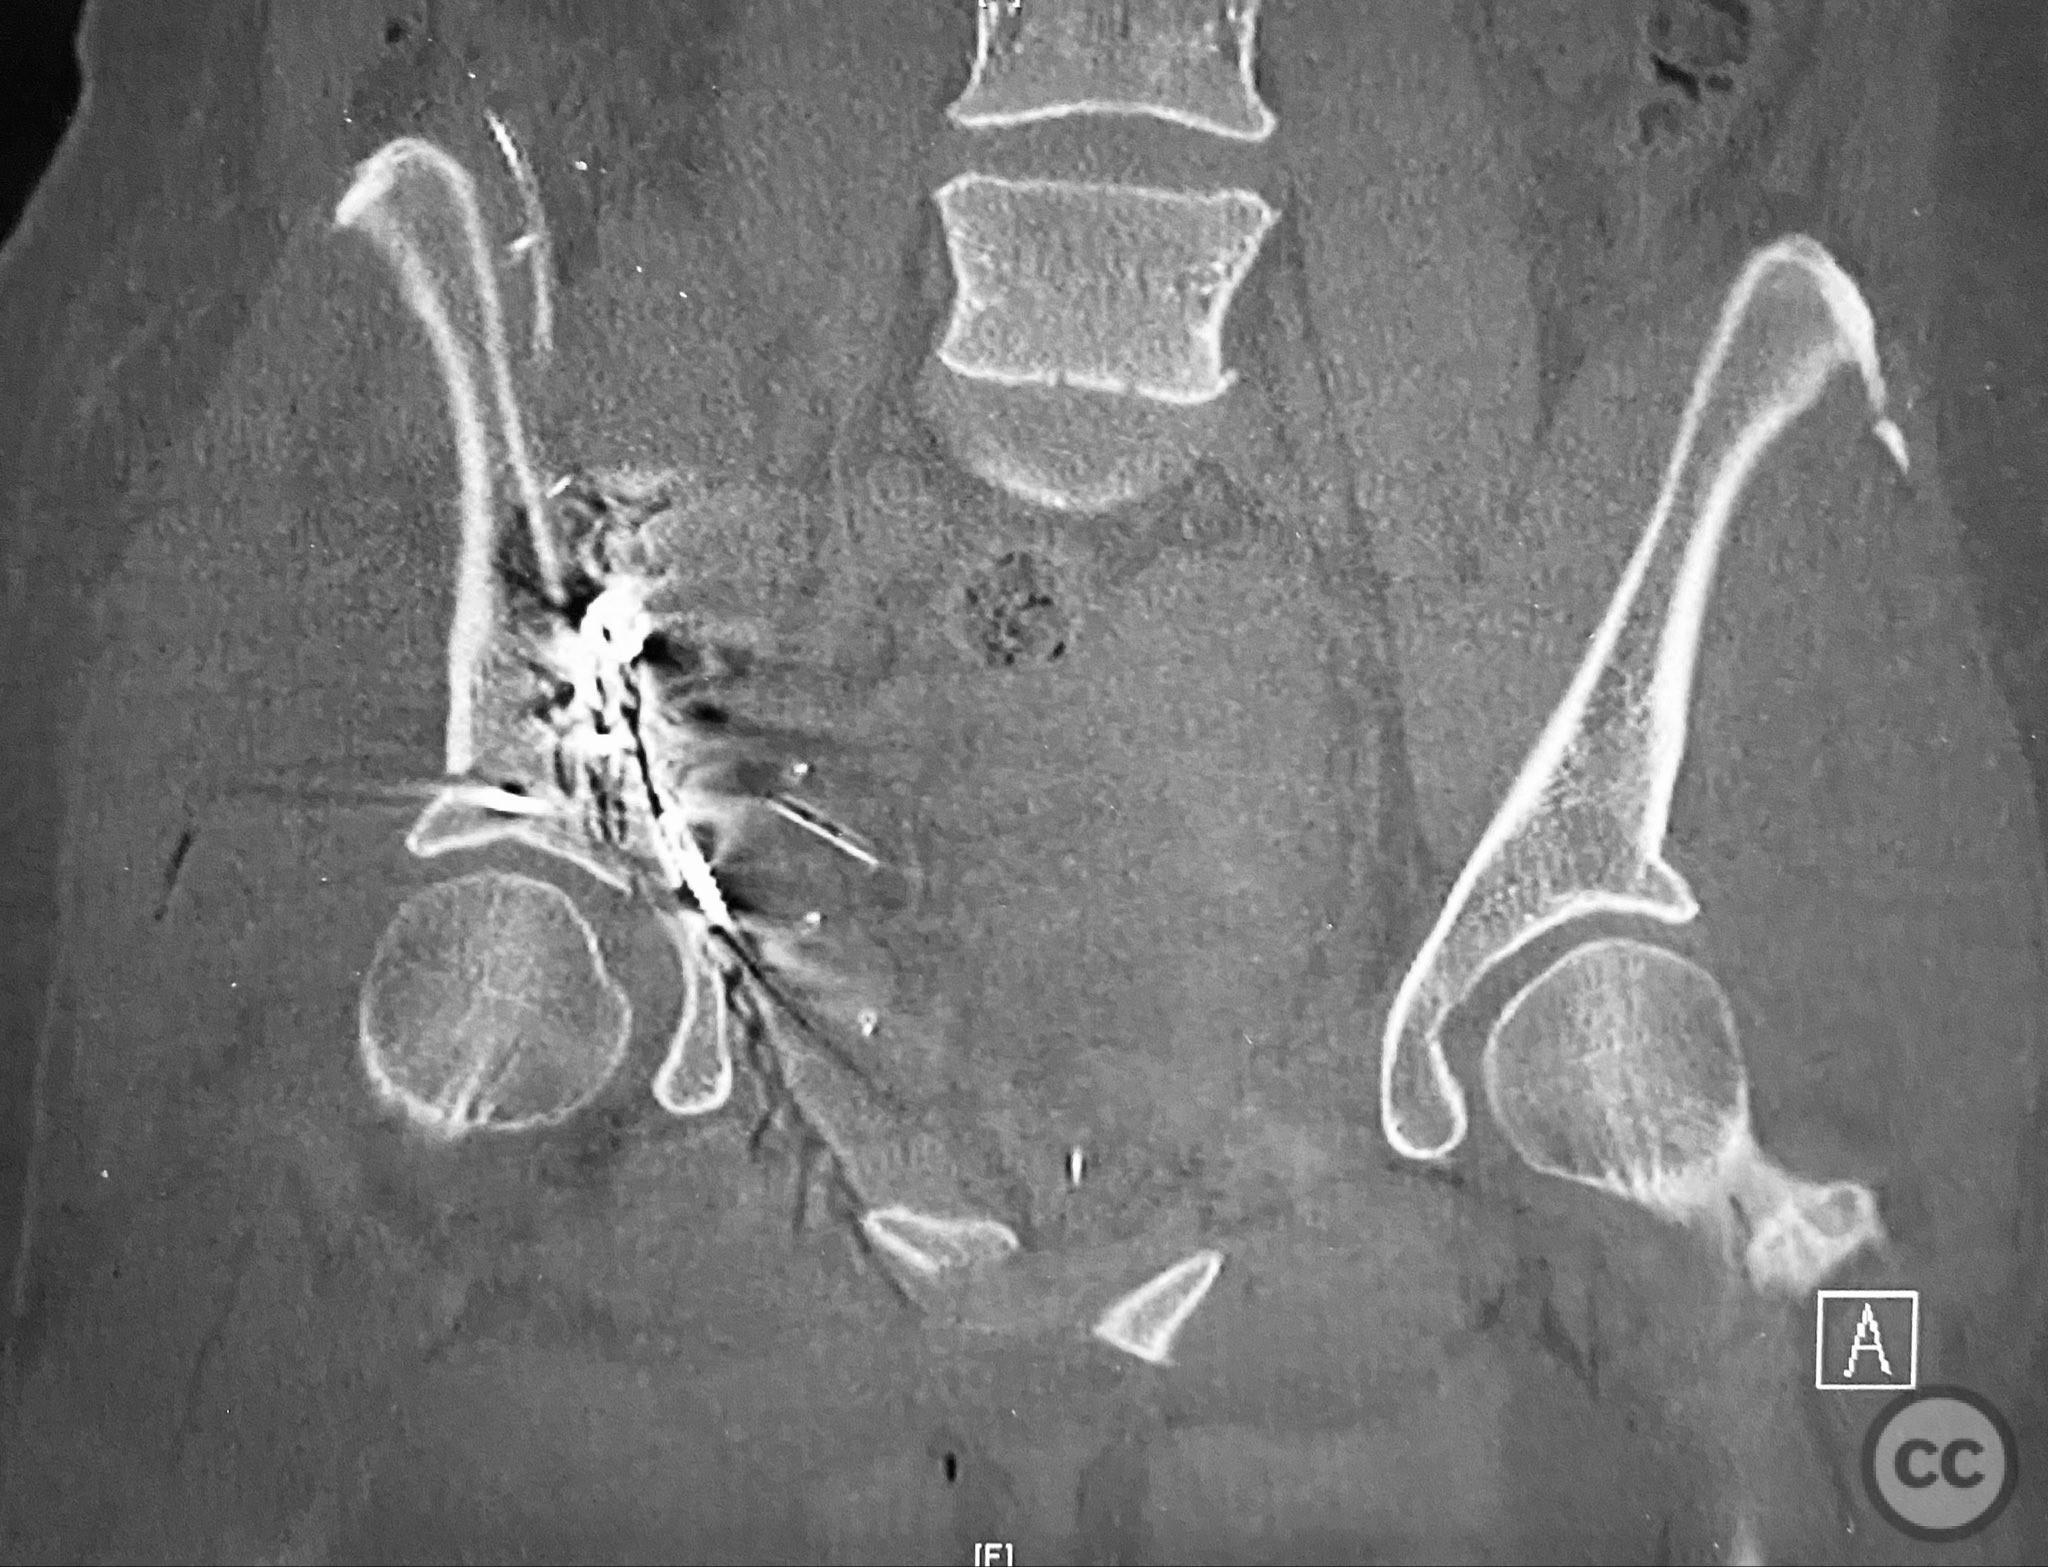

Clinical and radiological findings:  The patient sustained a complex both column acetabular fracture, AO/OTA 62C1, characterized by several large columnar fragments, an independent anterior inferior iliac spine (AIIS) fragment, a notable dome fragment predominantly attached to the posterior wall (PW) fragment, and a distinct parasymphyseal injury zone. Initial application of a pelvic binder resulted in increased displacement of the fracture fragments. Preoperative imaging, including surface renderings and multiplanar CT, demonstrated the independent AIIS fragment, detailed cortical surfaces, and the orientation of fracture planes. The majority of the acetabular dome was associated with the PW fragment, a critical detail for surgical planning and reduction.

Planning remarks:  The preoperative plan involved an ilioinguinal approach to facilitate direct visualization, cleaning, and reduction of the cortical and fracture surfaces. The reduction sequence was planned as follows: first, anatomical reduction and provisional fixation of the anterior column (AC) fragment using a 6-hole plate and lag screw; second, application of a 12-hole intrapelvic plate for additional stabilization; third, definitive stabilization of the posterior column (PC) and PW fragments with lag screws. No additional exposures were planned.

The anterior column fragment was reduced first under direct visualization and held with a 6-hole plate and lag screw. The 12-hole intrapelvic plate was then contoured and applied along the pelvic brim to reinforce the reduction. The posterior column and posterior wall fragments, including the dome component, were stabilized with lag screws placed through safe osseous corridors under fluoroscopic guidance. The independent AIIS fragment was addressed during the exposure and incorporated into the reduction construct. The parasymphyseal injury zone was inspected for stability following fixation. Postoperative CT confirmed anatomical reduction and stable fixation of all fragments.